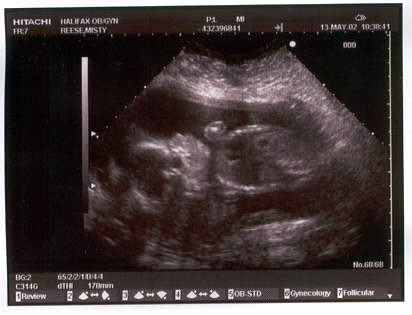

The ultrasound pictures (in May at 21 weeks):

A side view with the head at the left and body to the right with an arm at the top.